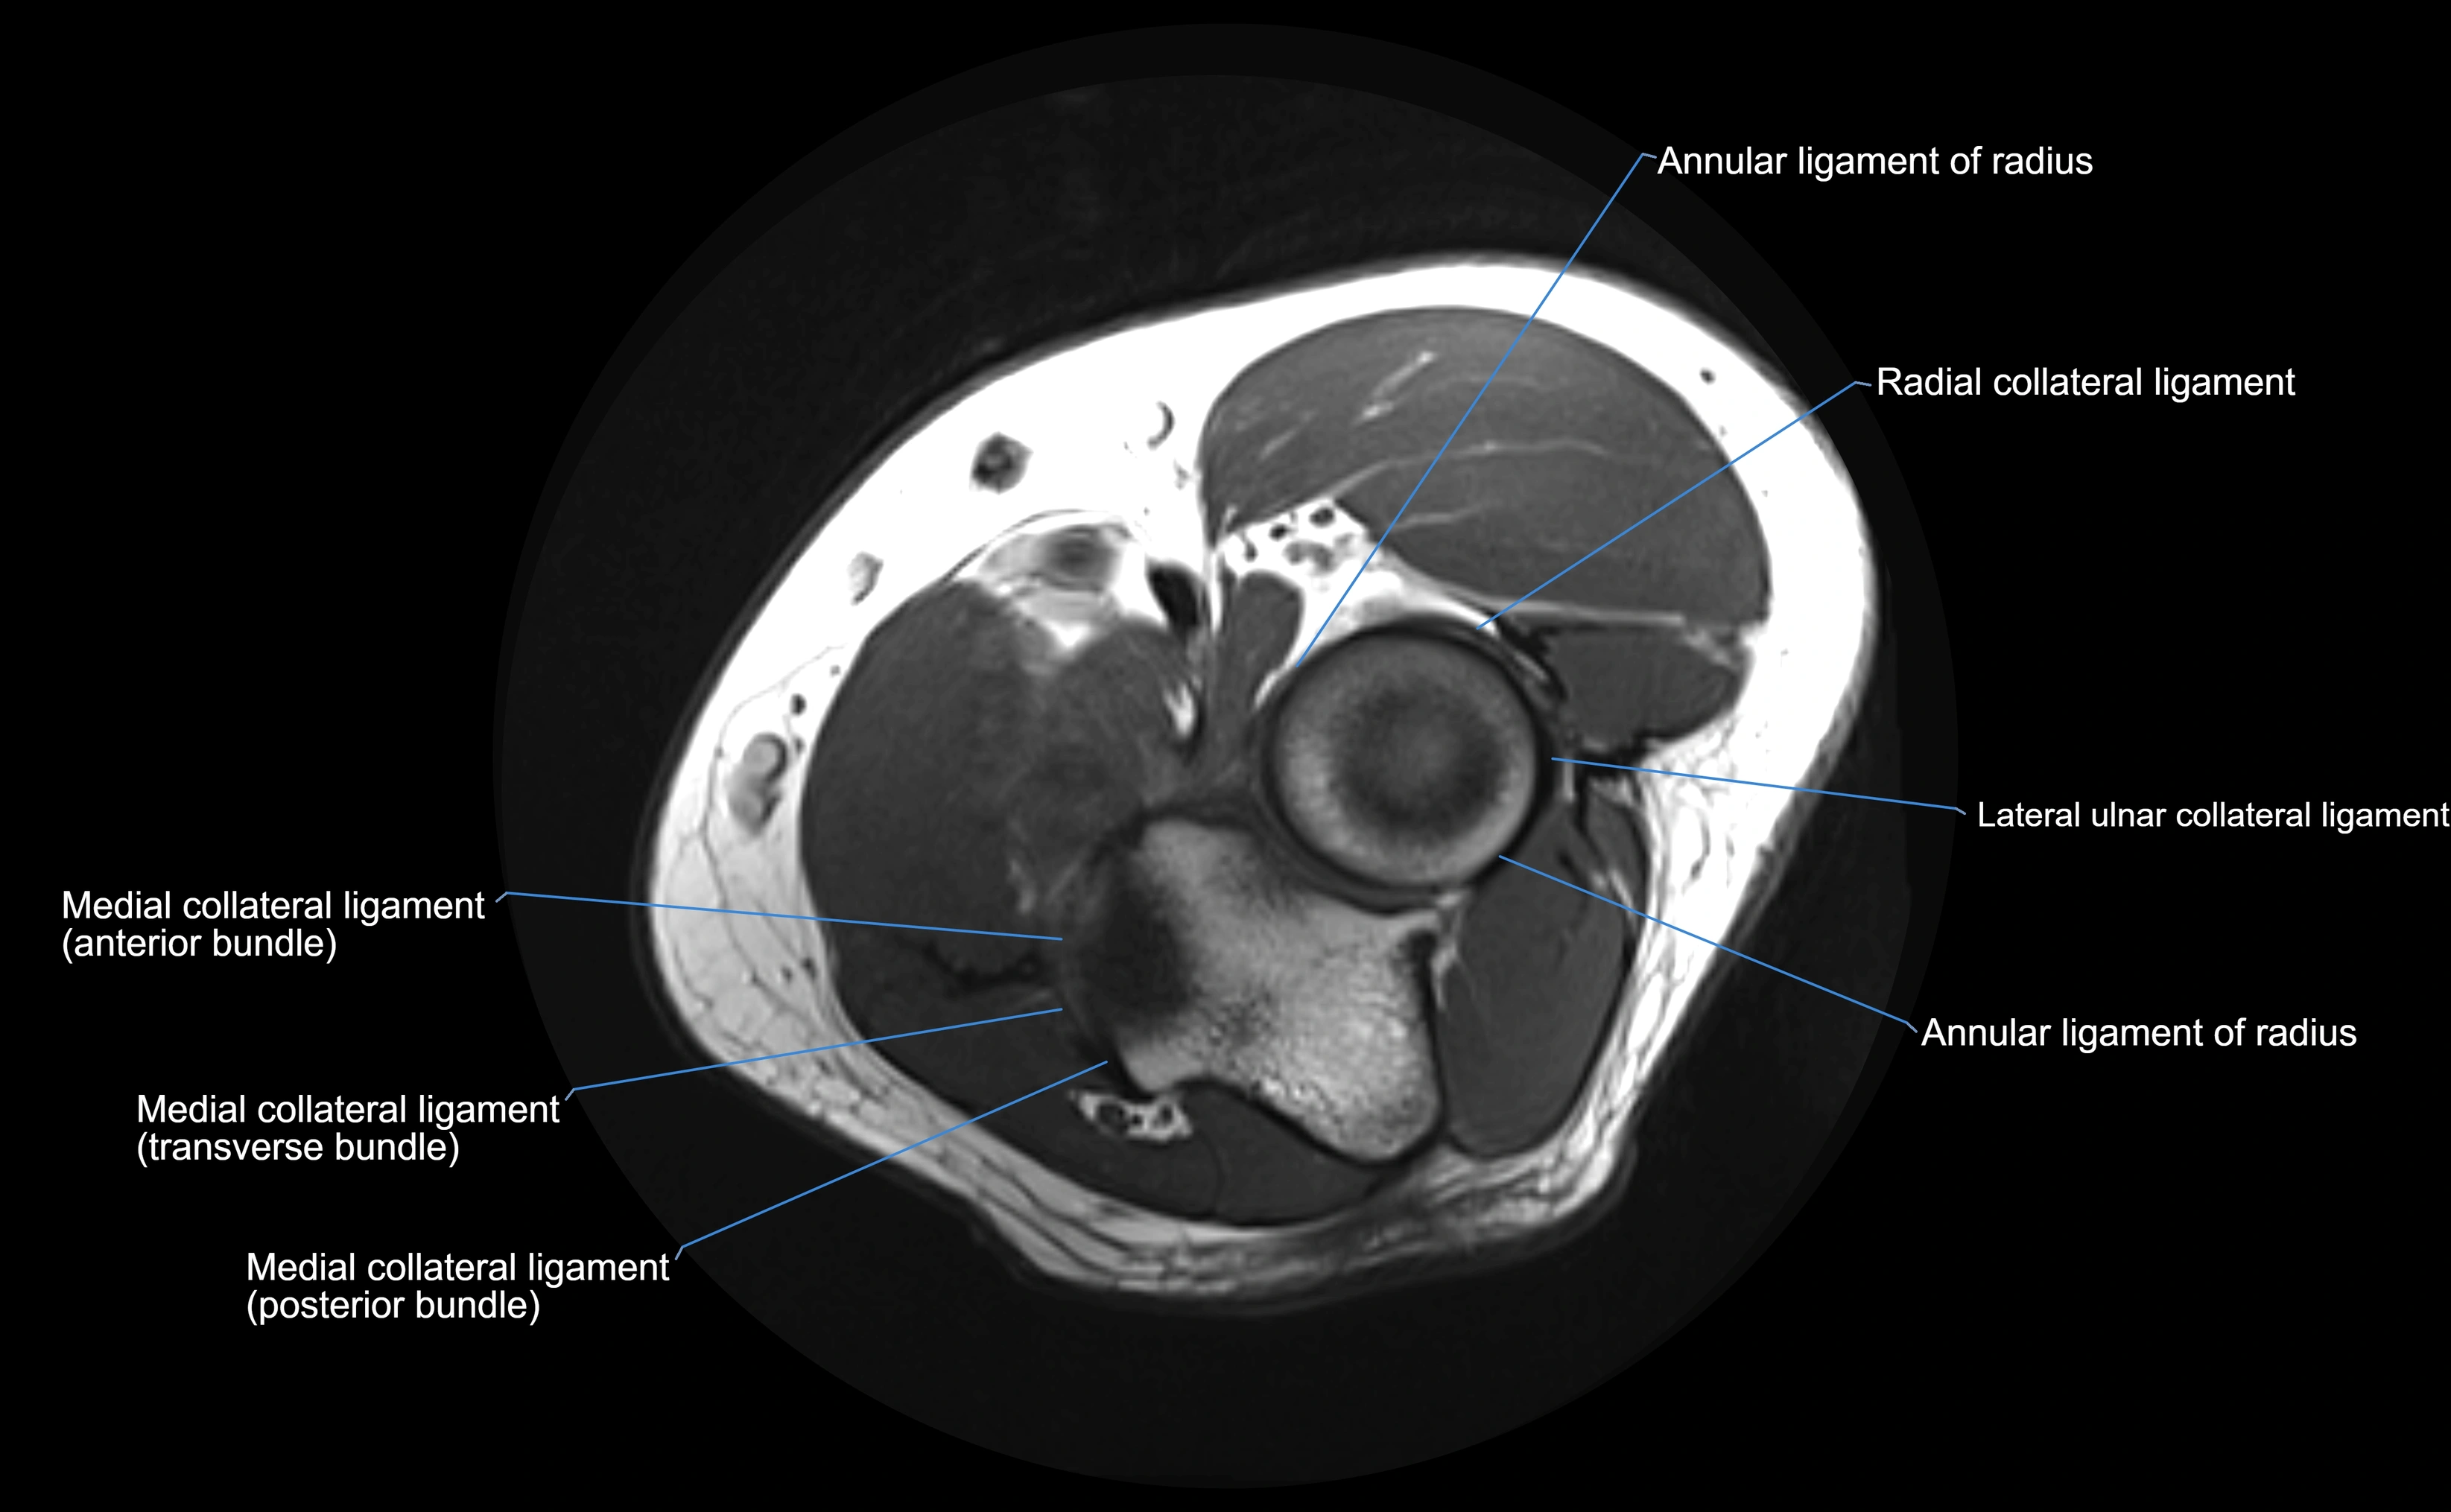

Annular ligament of radius

The annular ligament of the radius is a strong, circular band of fibers that encircles the head and neck of the radius, holding it securely against the radial notch of the ulna. It forms part of the proximal radioulnar joint, permitting smooth rotation of the radius during pronation and supination of the forearm.

The ligament acts like a collar or loop, maintaining radial head stability while allowing rotation. It is essential for forearm motion, elbow stability, and load transmission from the radius to the ulna and humerus.

MRI Appearance

T1-weighted images:

• Ligament: low signal intensity (dark), appearing as a continuous band around the radial head.

• Adjacent fat and marrow: bright, creating contrast with the ligament.

• Thickening or disruption indicates injury or fibrosis.

• Joint capsule and synovium seen as thin low-signal lines contiguous with ligament margins.

T2-weighted images:

• Ligament: low signal (dark) with clear delineation from joint fluid.

• Fluid or edema: bright hyperintense, separating or surrounding the ligament in partial tears.

• Complete tear: discontinuity or non-visualization of ligament fibers, often with joint effusion.

Proton Density Fat-Saturated (PD FS):

• Normal: dark, well-defined band outlining the radial head.

• Partial tear: irregular or bright hyperintense signal within or adjacent to ligament fibers.

• Joint effusion and reactive synovitis appear bright and are well visualized.